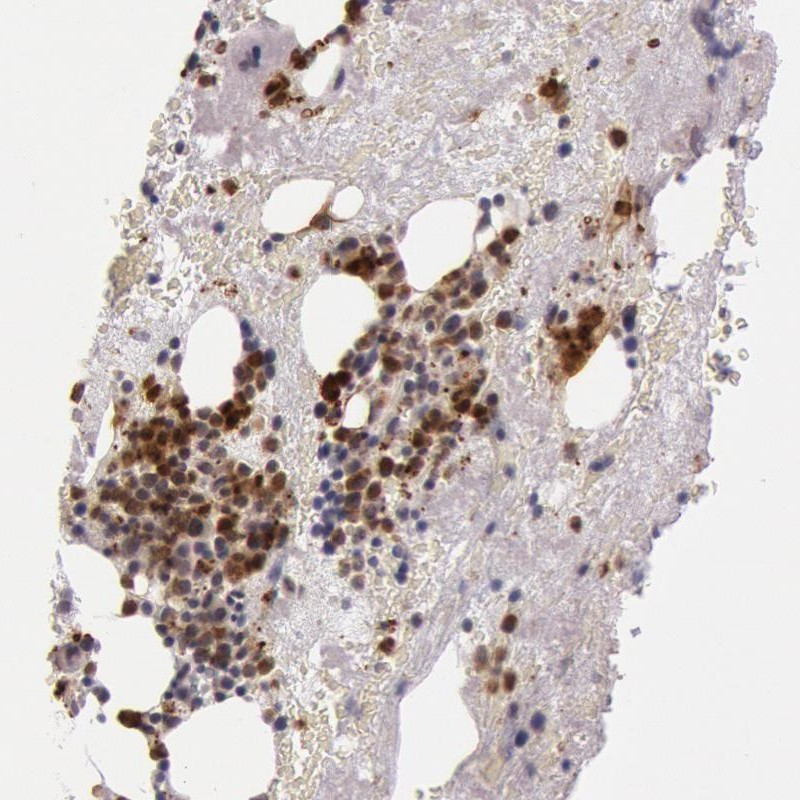

Immunohistochemical staining of human bone marrow shows distinct cytoplasmic positivity in subsets of hematopoietic cells.